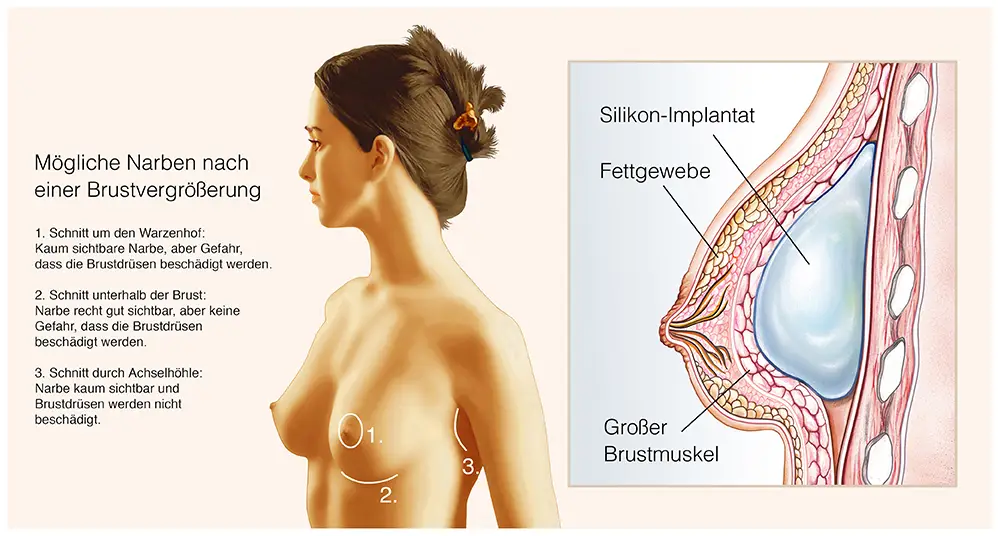

Der Ablauf umfasst folgende Schritte:

- Präzise Schnittführung (in der Brustumschlagfalte, um den Warzenhof oder in der Achselhöhle)

- Schaffung einer Implantattasche (unter der Brustdrüse oder unter dem Brustmuskel)

Die Narbenbildung nach einer Brustvergrößerung wird bei BB AESTHETIC – Plastic Surgery durch Dr. med. Mathias Bargellos spezielles Operationsverfahren minimiert:

- Strategische Schnittplatzierung unter BHs oder Bademode

- Fortschrittliche Nahttechniken für unauffälligere Narben

- Individueller Nachsorgeplan für optimale Wundheilung

- Ausführliche Beratung zur langfristigen Narbenpflege

Unser Experte Dr. med. Mathias Bargello bespricht die zu erwartende Narbenbildung und Optimierungsmöglichkeiten in Ihrem persönlichen Beratungsgespräch.